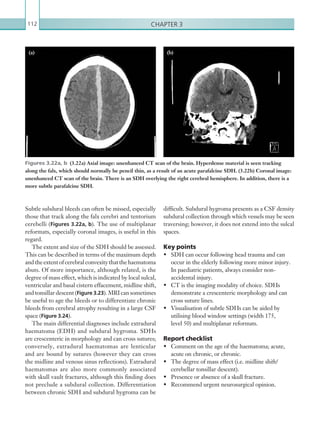

1.	 Create a VitalSource Bookshelf account at

https://online.vitalsource.com/user/new or log into

your existing account if you already have one.

2.	 Redeem the code provided in the panel below

to get online access to the ebook. Log in to

Bookshelf and click the Account menu at the top right

of the screen. Select Redeem and enter the redemption

code shown on the scratch-off panel below in the Code